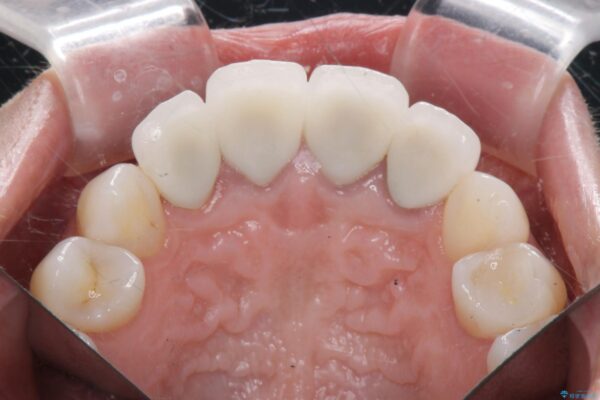

治療中

歯槽堤保存術を併用したブリッジ治療 治療中画像 歯槽堤保存術を併用したブリッジ治療 治療中画像 歯槽堤保存術を併用したブリッジ治療 治療中画像 歯槽堤保存術を併用したブリッジ治療 治療中画像 歯槽堤保存術を併用したブリッジ治療 治療中画像 歯槽堤保存術を併用したブリッジ治療 治療中画像 歯槽堤保存術を併用したブリッジ治療 治療中画像